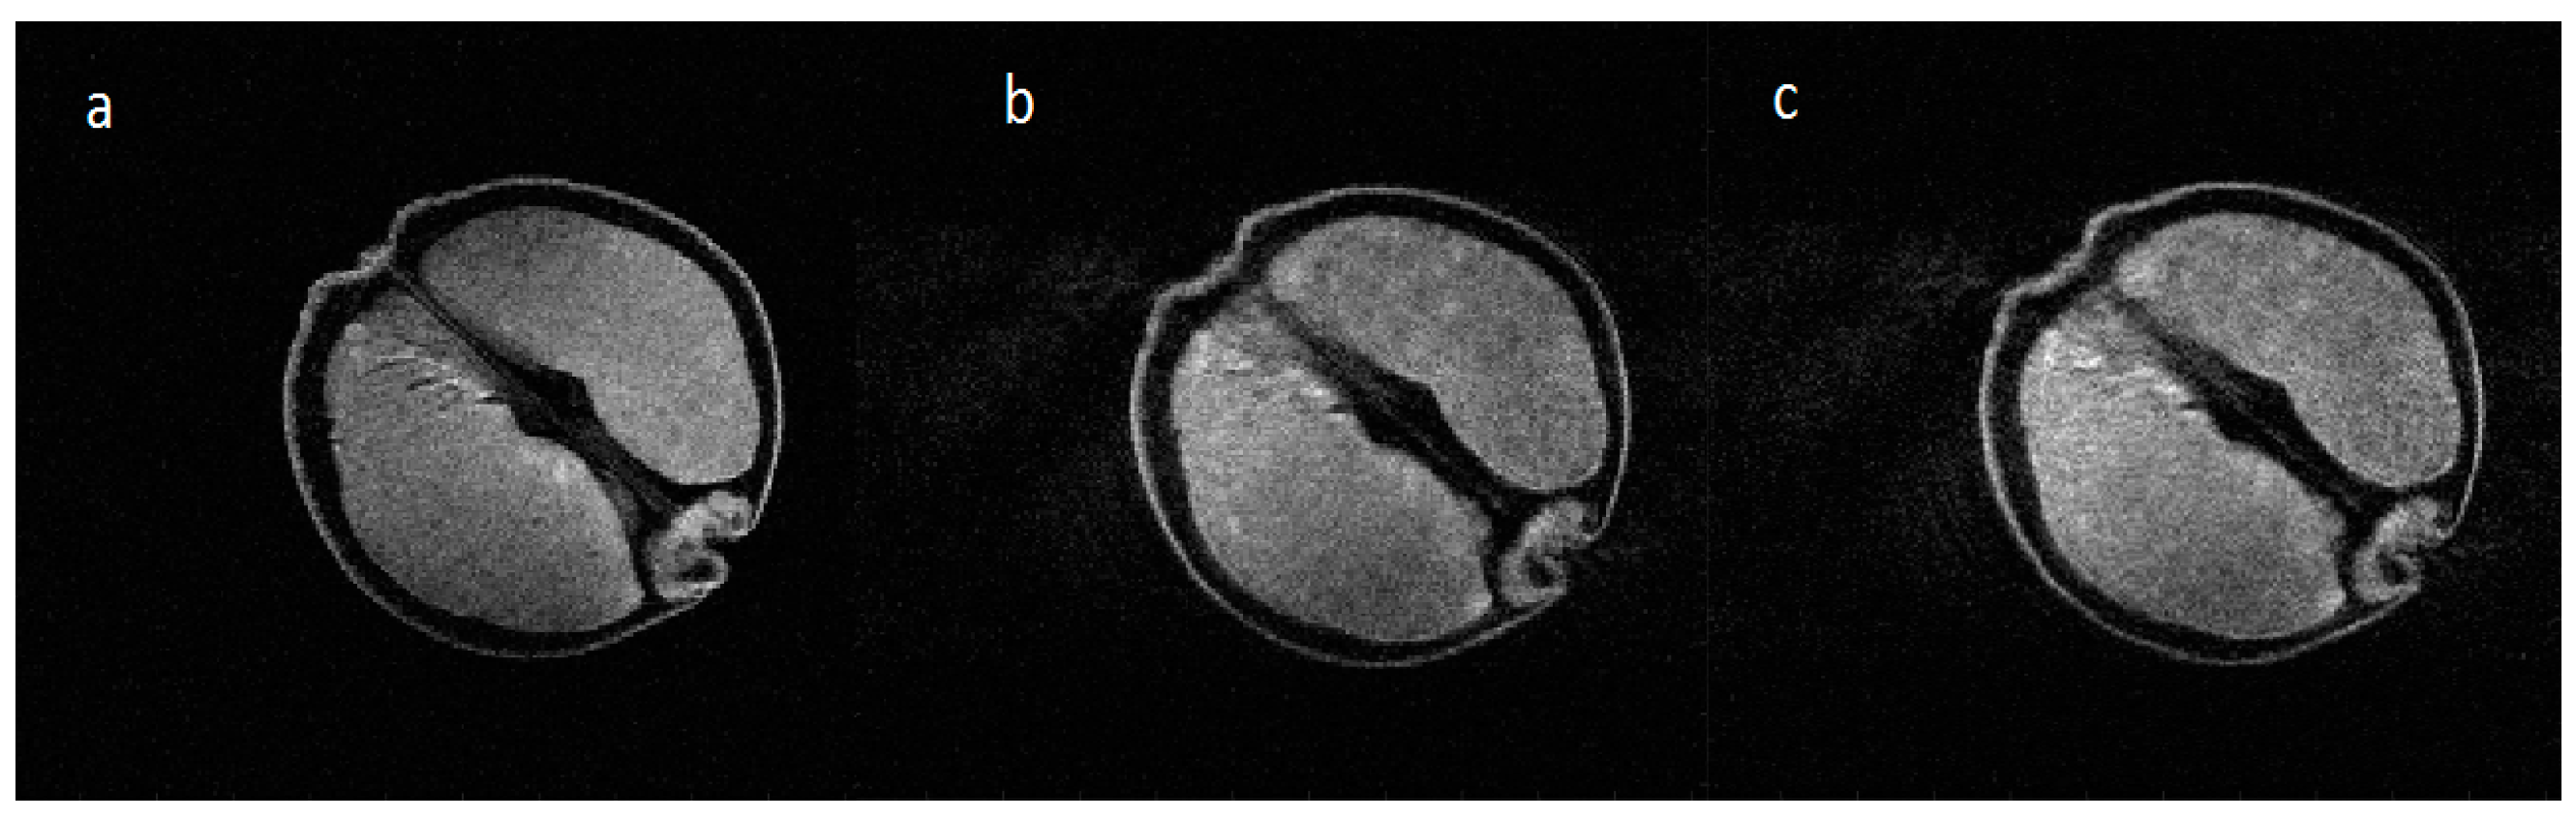

An example of relatively weak axial in-plane rotational motion of the test object (shown static in Figure 8a) is shown in Figure 8b, corresponding to the wireless accelerometer measurements shown in Figure 7b. The peak-to-peak angular variation was ~5 × 10−2 radians through the MR acquisition, similar to the simulation shown in Figure 6b. No artifacts from the radiofrequency or gradient pulses of the MR system are seen on the accelerometer traces. As the measurement is made totally independently from the MR scanner, there was no MR acquisition time penalty incurred. An attempt to correct the image motion artifact is shown in Figure 8c. Careful inspection of the internal segmental structure of the orange (dark lines) shows some subtle improvement in signal intensity assignment.

Figure 8. MR images of an orange acquired on the 3T neonatal MRI system with no in-plane angular motion (a) and pseudo-sinusoidal in-plane rotational motion about the iso-centre; (b) corresponding to the measurements shown above in Figure 7; (c) an attempt to remove the motion using the measured rotation angles shows some subtle improvement of image quality.